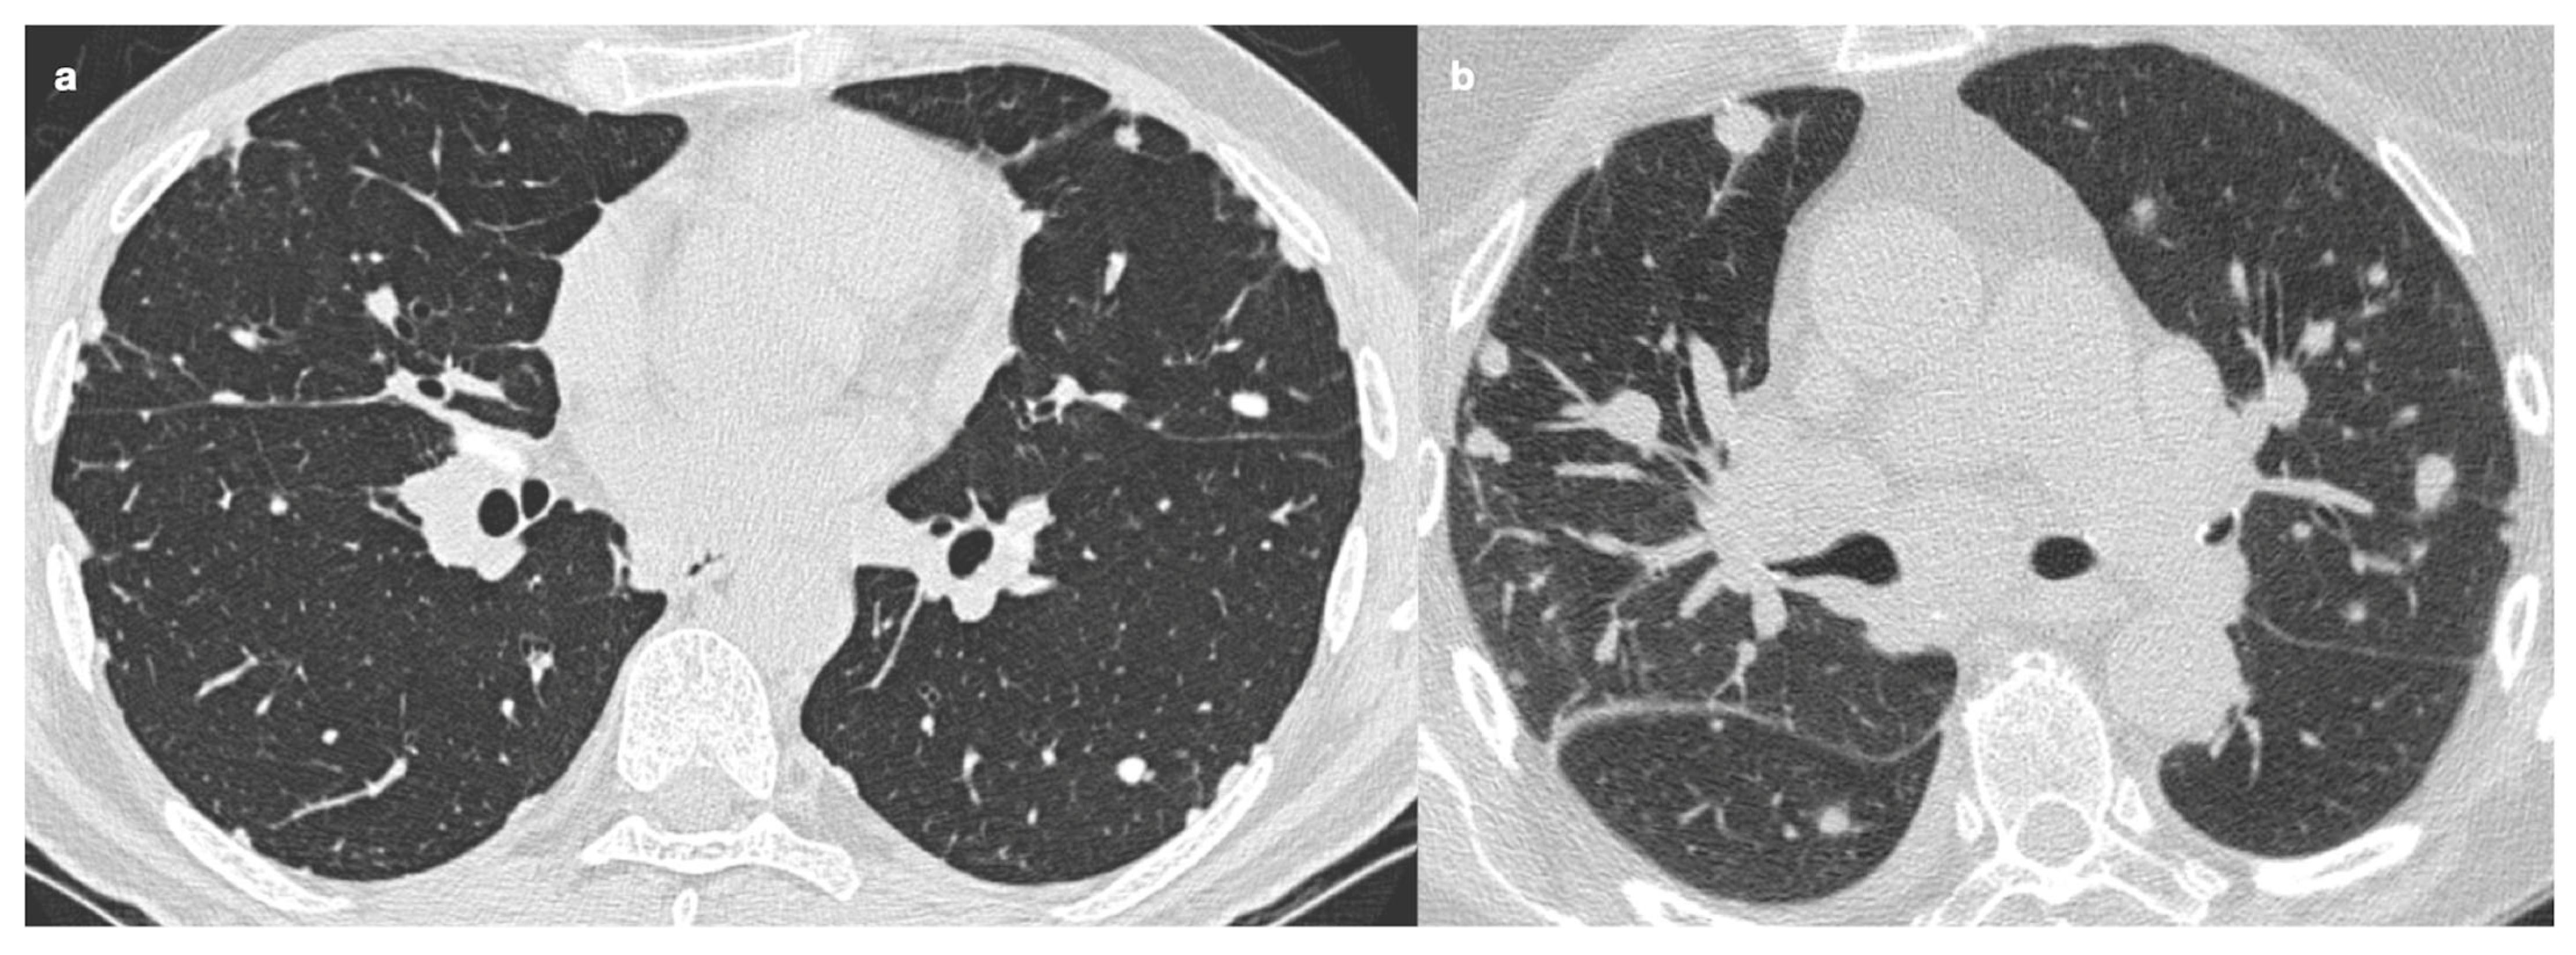

4.1. Typical Imaging

4.2. Atypical Imaging

| Distribution | Perilympathic (75–90% of cases); bilateral and symmetric involvement, especially in the middle and upper lobes |

| Nodule size | Micronodules 2–4 mm in diameter |

| Morphology | Nodules with well-defined margins, round shape |

| HRCT localization | Peribronchovascular interstitium, interlobar fissures, interlobular septa |

| Evolution | Possible coalescence of micronodules into macronodules over time |